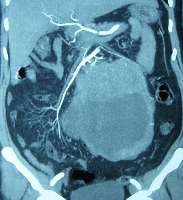

Πρόκειται για γυναίκα ασθενή 55 ετών η οποία, στα πλαίσια διερεύνησης αιμορραγίας ανώτερου πεπτικού, υποβλήθηκε σε απεικονιστικές εξετάσεις που ανέδειξαν οπισθοπεριτοναϊκό όγκο μεγέθους μεγαλύτερου των 20 cm, που εξορμούνταν από το δωδεκαδάκτυλο (εικόνα 1). Εγχειρητικά, εκτός από την εμπλοκή της 3ης & 4ης δωδεκαδακτυλικής μοίρας, διαπιστώθηκε ότι ο όγκος ενέπλεκε και τη μεσότητα του αριστερού ουρητήρα. Η παθολογοανατομική εκτίμηση του en bloc παρασκευάσματος (εικόνα 2) ανέδειξε την ύπαρξη GIST (80 μιτώσεις ανά 50 ΟΠ Χ 400). Η ανατομική αποκατάσταση πραγματοποιήθηκε με τελικο-τελική ουρητηρο-ουρητηροστομία (εικόνα 3) και πλαγιο-πλάγια δωδεκαδακτυλο-νηστιδοστομία (εικόνα 4). Η μετεγχειρητική αξονική τομογραφία ανέδειξε άθικτα μεσεντέρια αγγεία (εικόνα 5). Η ασθενής έλαβε εξιτήριο την 6η μετεγχειρητική ημέρα. Βρίσκεται σε αγωγή με Gleevec και εξακολουθεί να παραμένει ελεύθερη νόσου.